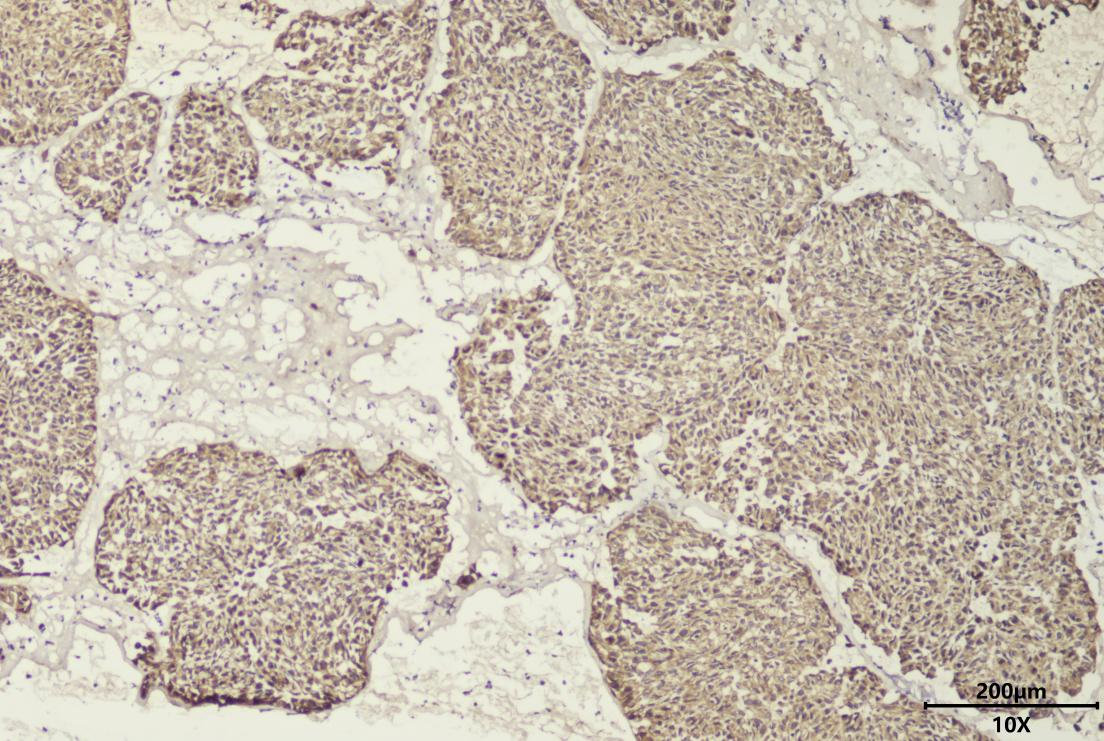

肺神经内分泌瘤术中冰冻CK免疫组化染色